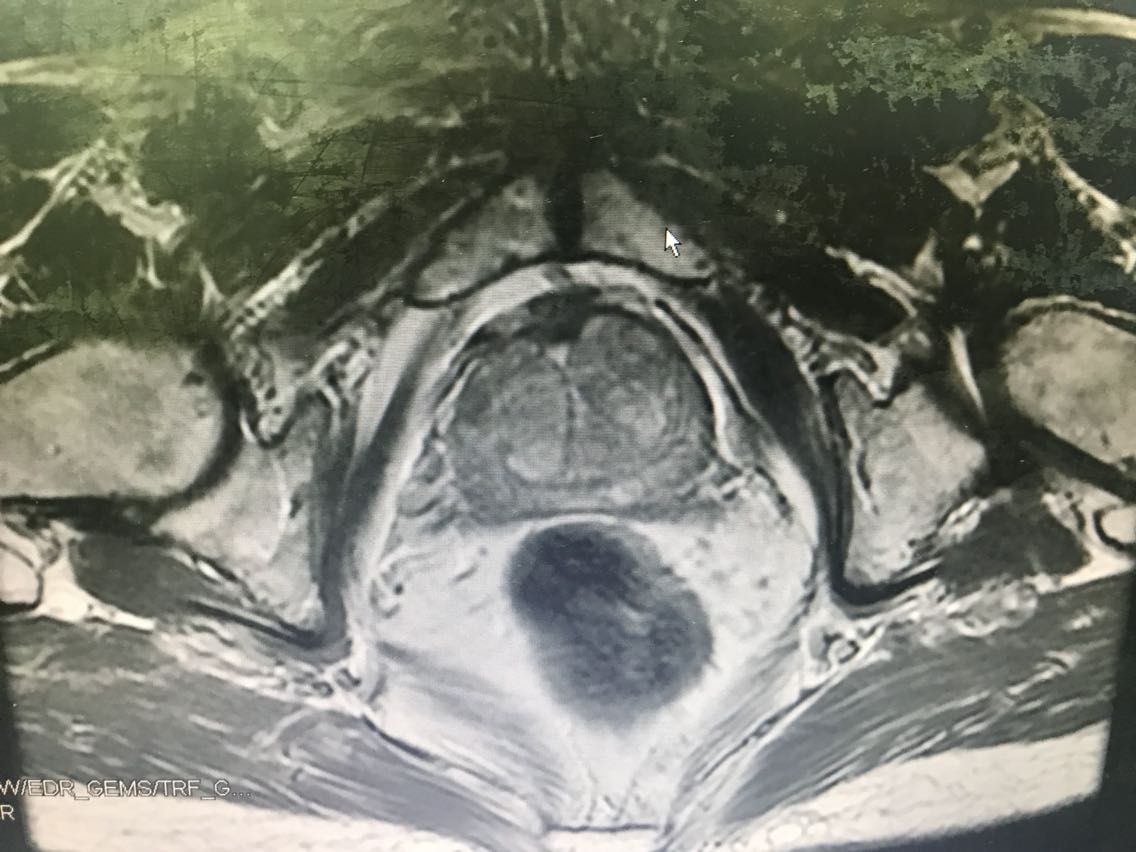

患者男性,77岁。 主诉:血尿7+月 现病史:入院前7+月,患者出现血尿,于外院体检查示PSA升高(10.62),服药血尿控制(具体药物不详),无尿频、尿急、下腹疼痛等不适,为求进一步诊治于我院门诊就诊,查前列腺MRI:前列腺尖部右侧中央带结节及9-10点结节,多系前列腺癌。门诊行前列腺穿刺活检示:编号1、2、3、4、5、6查见前列腺腺癌,Gleason评分4+3=7分。门诊以“前列腺癌”收入我科。患病来精神、睡眠、食欲可,大小便无异常,体重无明显变化。 既往史无特殊。

查体:腹部平软,无压痛及反跳痛,双肾及输尿管走行区无压痛,肾区无叩痛。直肠指检:前列腺Ⅱ°大,双侧质硬,右侧叶扪及约1cm硬结。 辅助检查: 前列腺MRI(2018-6-14,本院):前列腺尖部右侧中央带结节及9-10点结节,多系前列腺癌,累及右侧外周带 前列腺穿刺活检示(2018-6-28,本院):编号1、2、3、4、5、6查见前列腺腺癌,Gleason评分4+3=7分。